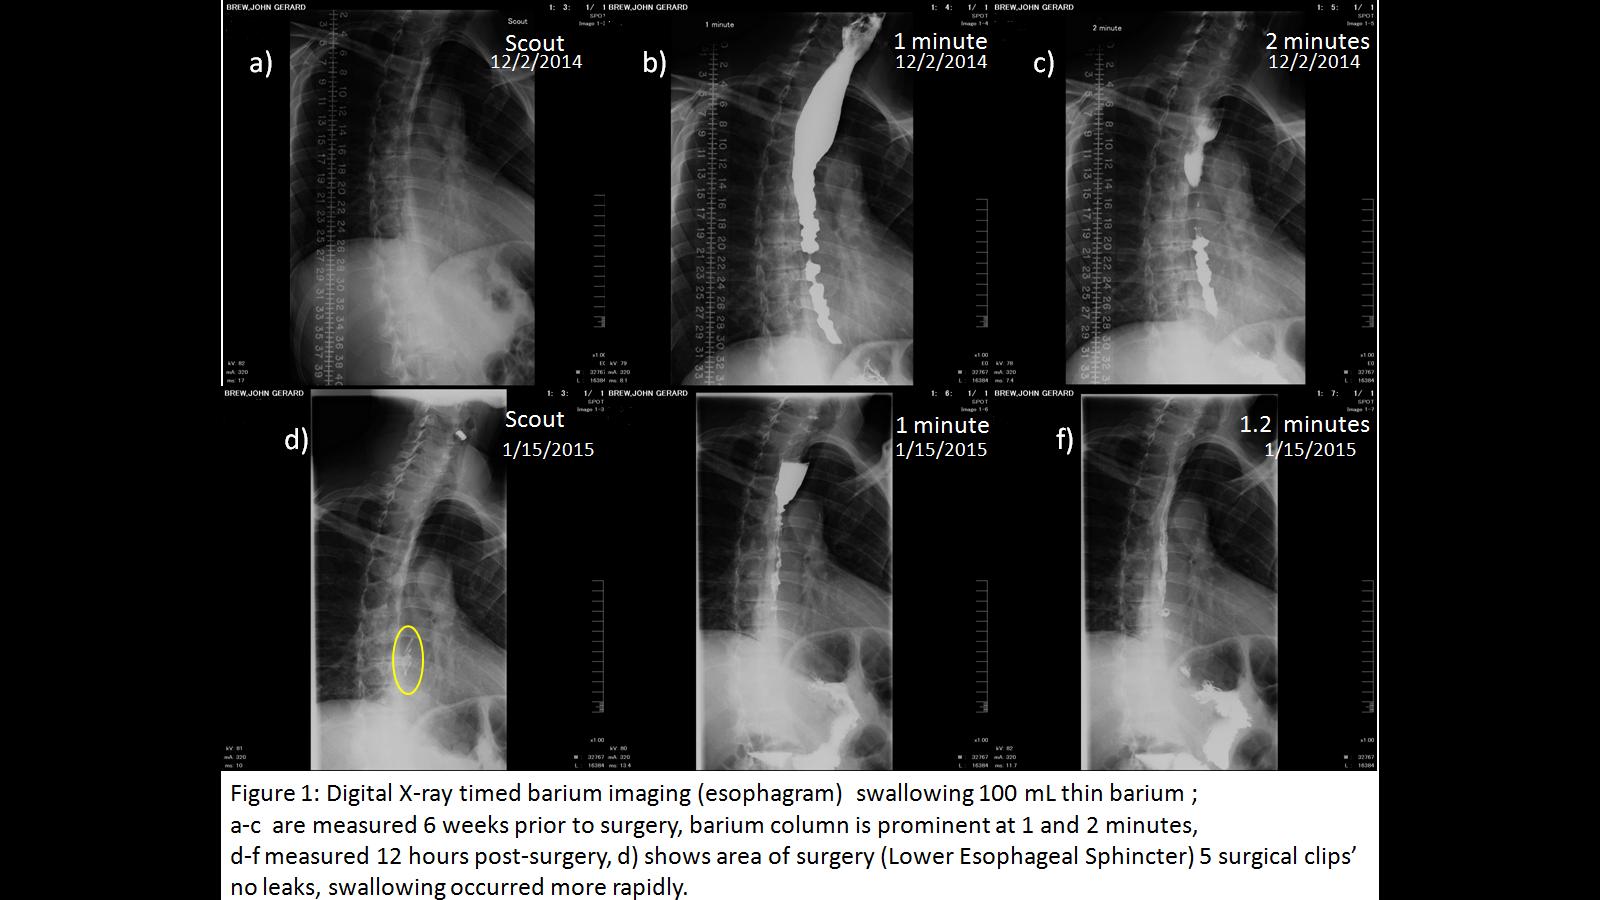

Here is an example of a normal barium swallow study, in which the barium (the dark liquid) is seen moving down the esophagus without any leakage or regurgitation (reflux):

Share on Pinterest

Photo: Anka Friedrich / commons.wikimedia.org